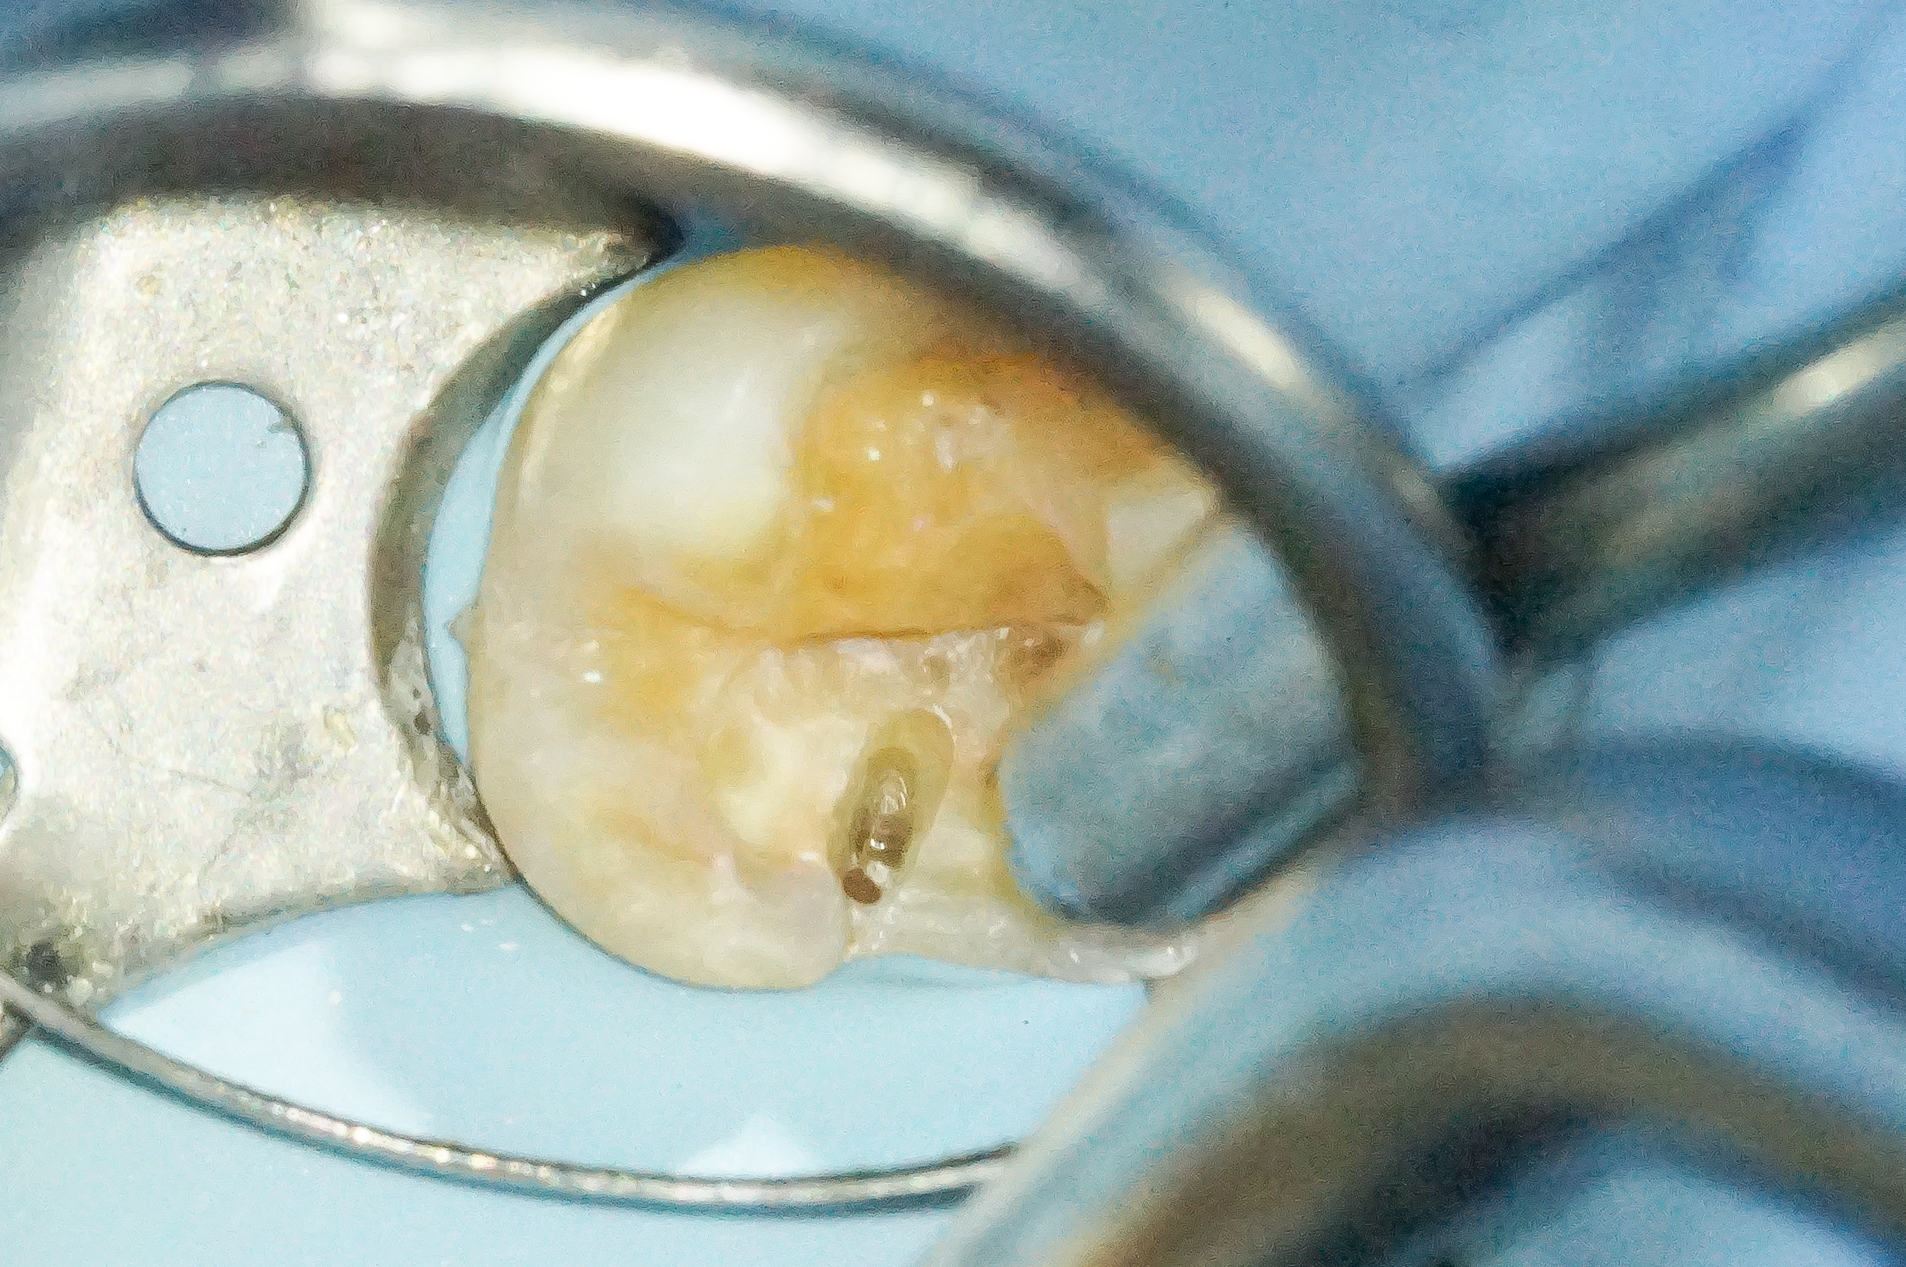

マイクロスコープで丁寧に観察すると歯の破折が見られました。

可及的に掘り進め、歯へのダメージを最小限に、尚且つクラック部からの細菌感染の防止ができるように作業を行いました。

ウ蝕を取りきることができたので被せの土台を作っていきます。

長期的に歯に問題が起きにくいオーバーレイの形で形成を行いました。

「オーバーレイ治療」はクラウン治療では削りすぎ、インレー治療では欠けてしまう可能性がある症例に非常に有効です。